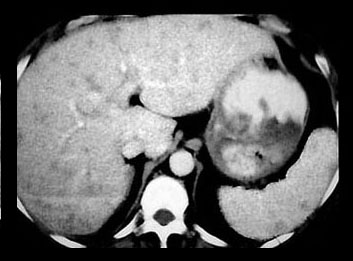

Hepatomegaly and splenomegaly occur in about one-third of patients. Liver lesions have been found in about 5% and spleen lesions 2-3 times as often in patients with sarcoidosis undergoing computed tomography examinations. The liver and spleen lesions most often appear as small widespread foci of decreased attenuation best seen when intravenous contrast material is utilized.

The small low attenuation lesions in the liver and spleen in sarcoidosis.